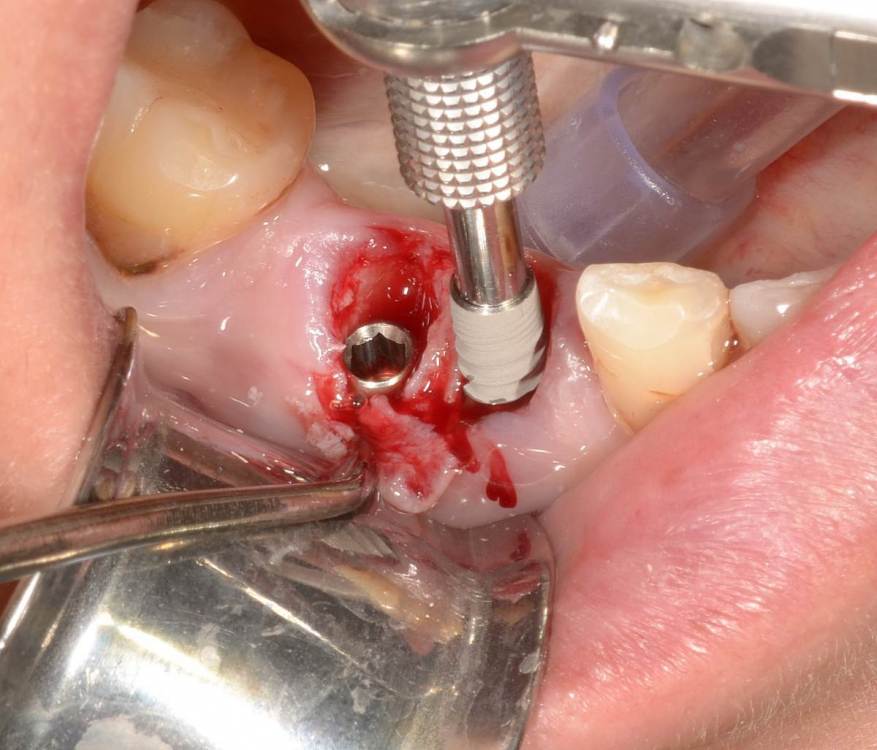

Большой Зеленый Опубликовано 19 мая, 2022 Поделиться Опубликовано 19 мая, 2022 По кт конечно. И очень важно атравматично удалить зуб не сломав перегородку. Я после рассечения корней прохожу пилотом .Если есть шаблон то еще лучше ,не соскользнет сверло. Сверху закрываю PRF мембранками 1 Ссылка на комментарий

Большой Зеленый Опубликовано 20 мая, 2022 Поделиться Опубликовано 20 мая, 2022 Примерно 80 процентов . Просто не всегда удается сохранить перегородку . Она вроде бы есть ,а на деле все выгнило. Очень часто это не просто трещины корня, это огромные дефекты . Смысла нет толкать имплант в гной.. Ссылка на комментарий

Большой Зеленый Опубликовано 27 мая, 2022 Поделиться Опубликовано 27 мая, 2022 4 часа назад, pit сказал: Это связано исключительно с вестибулярной позицией импланта. Это как раз к вопросу про те минимальные 2мм до вестиболярной стенки, вне зависимости есть она или ты ее создаешь. С тех пор я стал хитрее умнее и опытнее ))) 1 час назад, alboard сказал: А в чем смысл ее сохранности, если препарируя под имплантат вы все равно ее в большинстве случаев сносите? Первичная стабильность импланта зачастую достигается только перегородкой.. Ссылка на комментарий